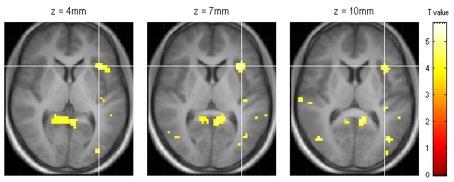

Figure 1.

Activation in the insula is increased when the stomach is distended more.

This novel approach - combining information obtained simultaneously from MRI images of the stomach, feelings reported by the subjects, and brain scans - can offer new insights which would otherwise have been unknown, for example that activation in a brain area called the mid-temporal gyrus seems is in some way influenced by the increased water load in this experiment. The Wageningen University scientists developed the combined MRI method as part of the European Nudge-it research project, which seeks to discover simple changes that promote healthier eating. They will use it to search for a brain signature that leads people to decide to stop eating, to determine how strategies like water with a meal can be effective at feeling fuller sooner.